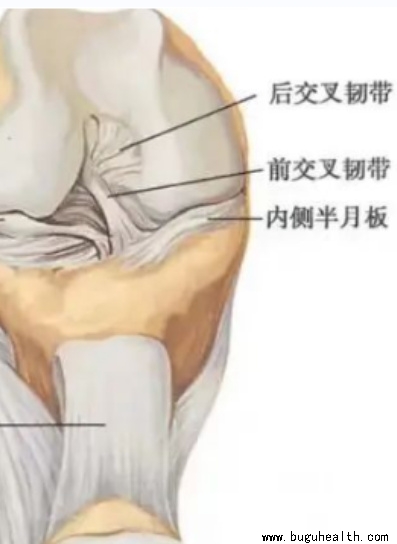

- 半月板是膝关节内胫骨和股骨间隙内的纤维性板状软骨组织,外观呈“C”型,故称为半月板。位于膝关节内侧的叫做内侧半月板,类似“C”型,外侧的叫做外侧半月板,类似“O”型。其中内侧半月板与关节囊周边连接紧密,活动性差。外侧半月板后角存在腘肌腱裂隙,活动度略大。半月板在关节内伴随膝关节一起运动,可以起到缓冲.....

- 前交叉韧带重建术后早期最重要的两件事:1.能够完全伸直膝关节;2.激活股四头肌。如果你术后早期就注意这两个问题,这一点都不难,很轻松就可以达到。但如果很不巧,你在早期这两个方面没恢复好的话,后期会非常的麻烦。而且更重要的是,这两者之间是紧密联系的,往往一个不好,另外一个也就不好。.....